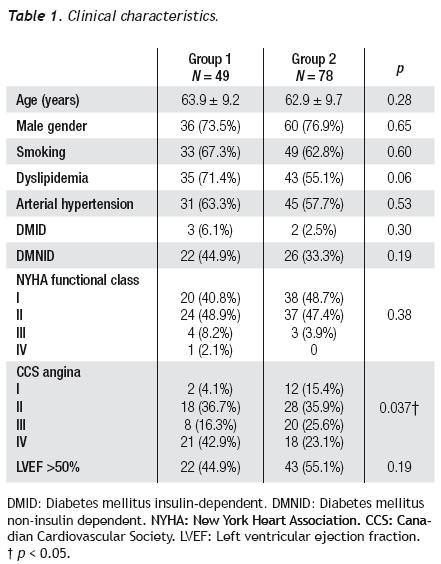

The clinical characteristics of both groups are presented in Table 1. Average age was 63.9 ± 9.2 years for group 1 and 62.9 ± 9.7 years for group 2 (p = 0.28). We observed no differences in risk factors, such as diabetes mellitus, arterial hypertension, smoking, and dyslipidemia between both groups. The ejection fraction and NYHA functional class were similar in both groups (p = 0.19 and p = 0.38). Angina class III/IV and CCS were more frequent in group 1 than in group 2 (59.2% vs. 48.7%, p = 0.026), and the time elapsed from CABG to PCI was greater in group 1 (8.7 ± 5.6 years vs. 5.7 ± 4.1 years, p = 0.001).